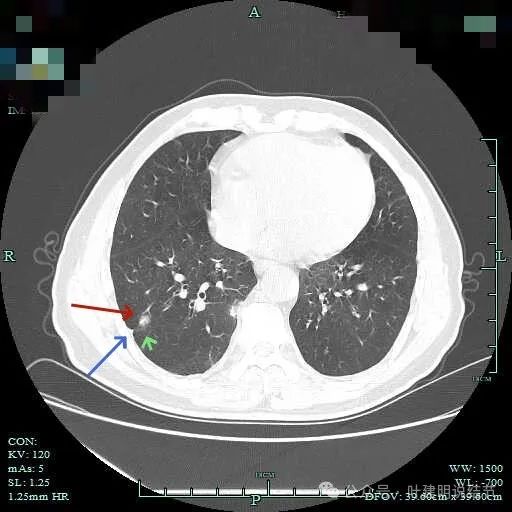

密度较高,确实像血管进入。但病灶片状,趴在脊柱上。

此层显得更呈小片状了。

与脊柱间似乎有间隙在,另见微小血管进入这条索状的偏高密度影处。

有细小血管进入,但说不上异常增粗。病灶仍是小片状,条状。